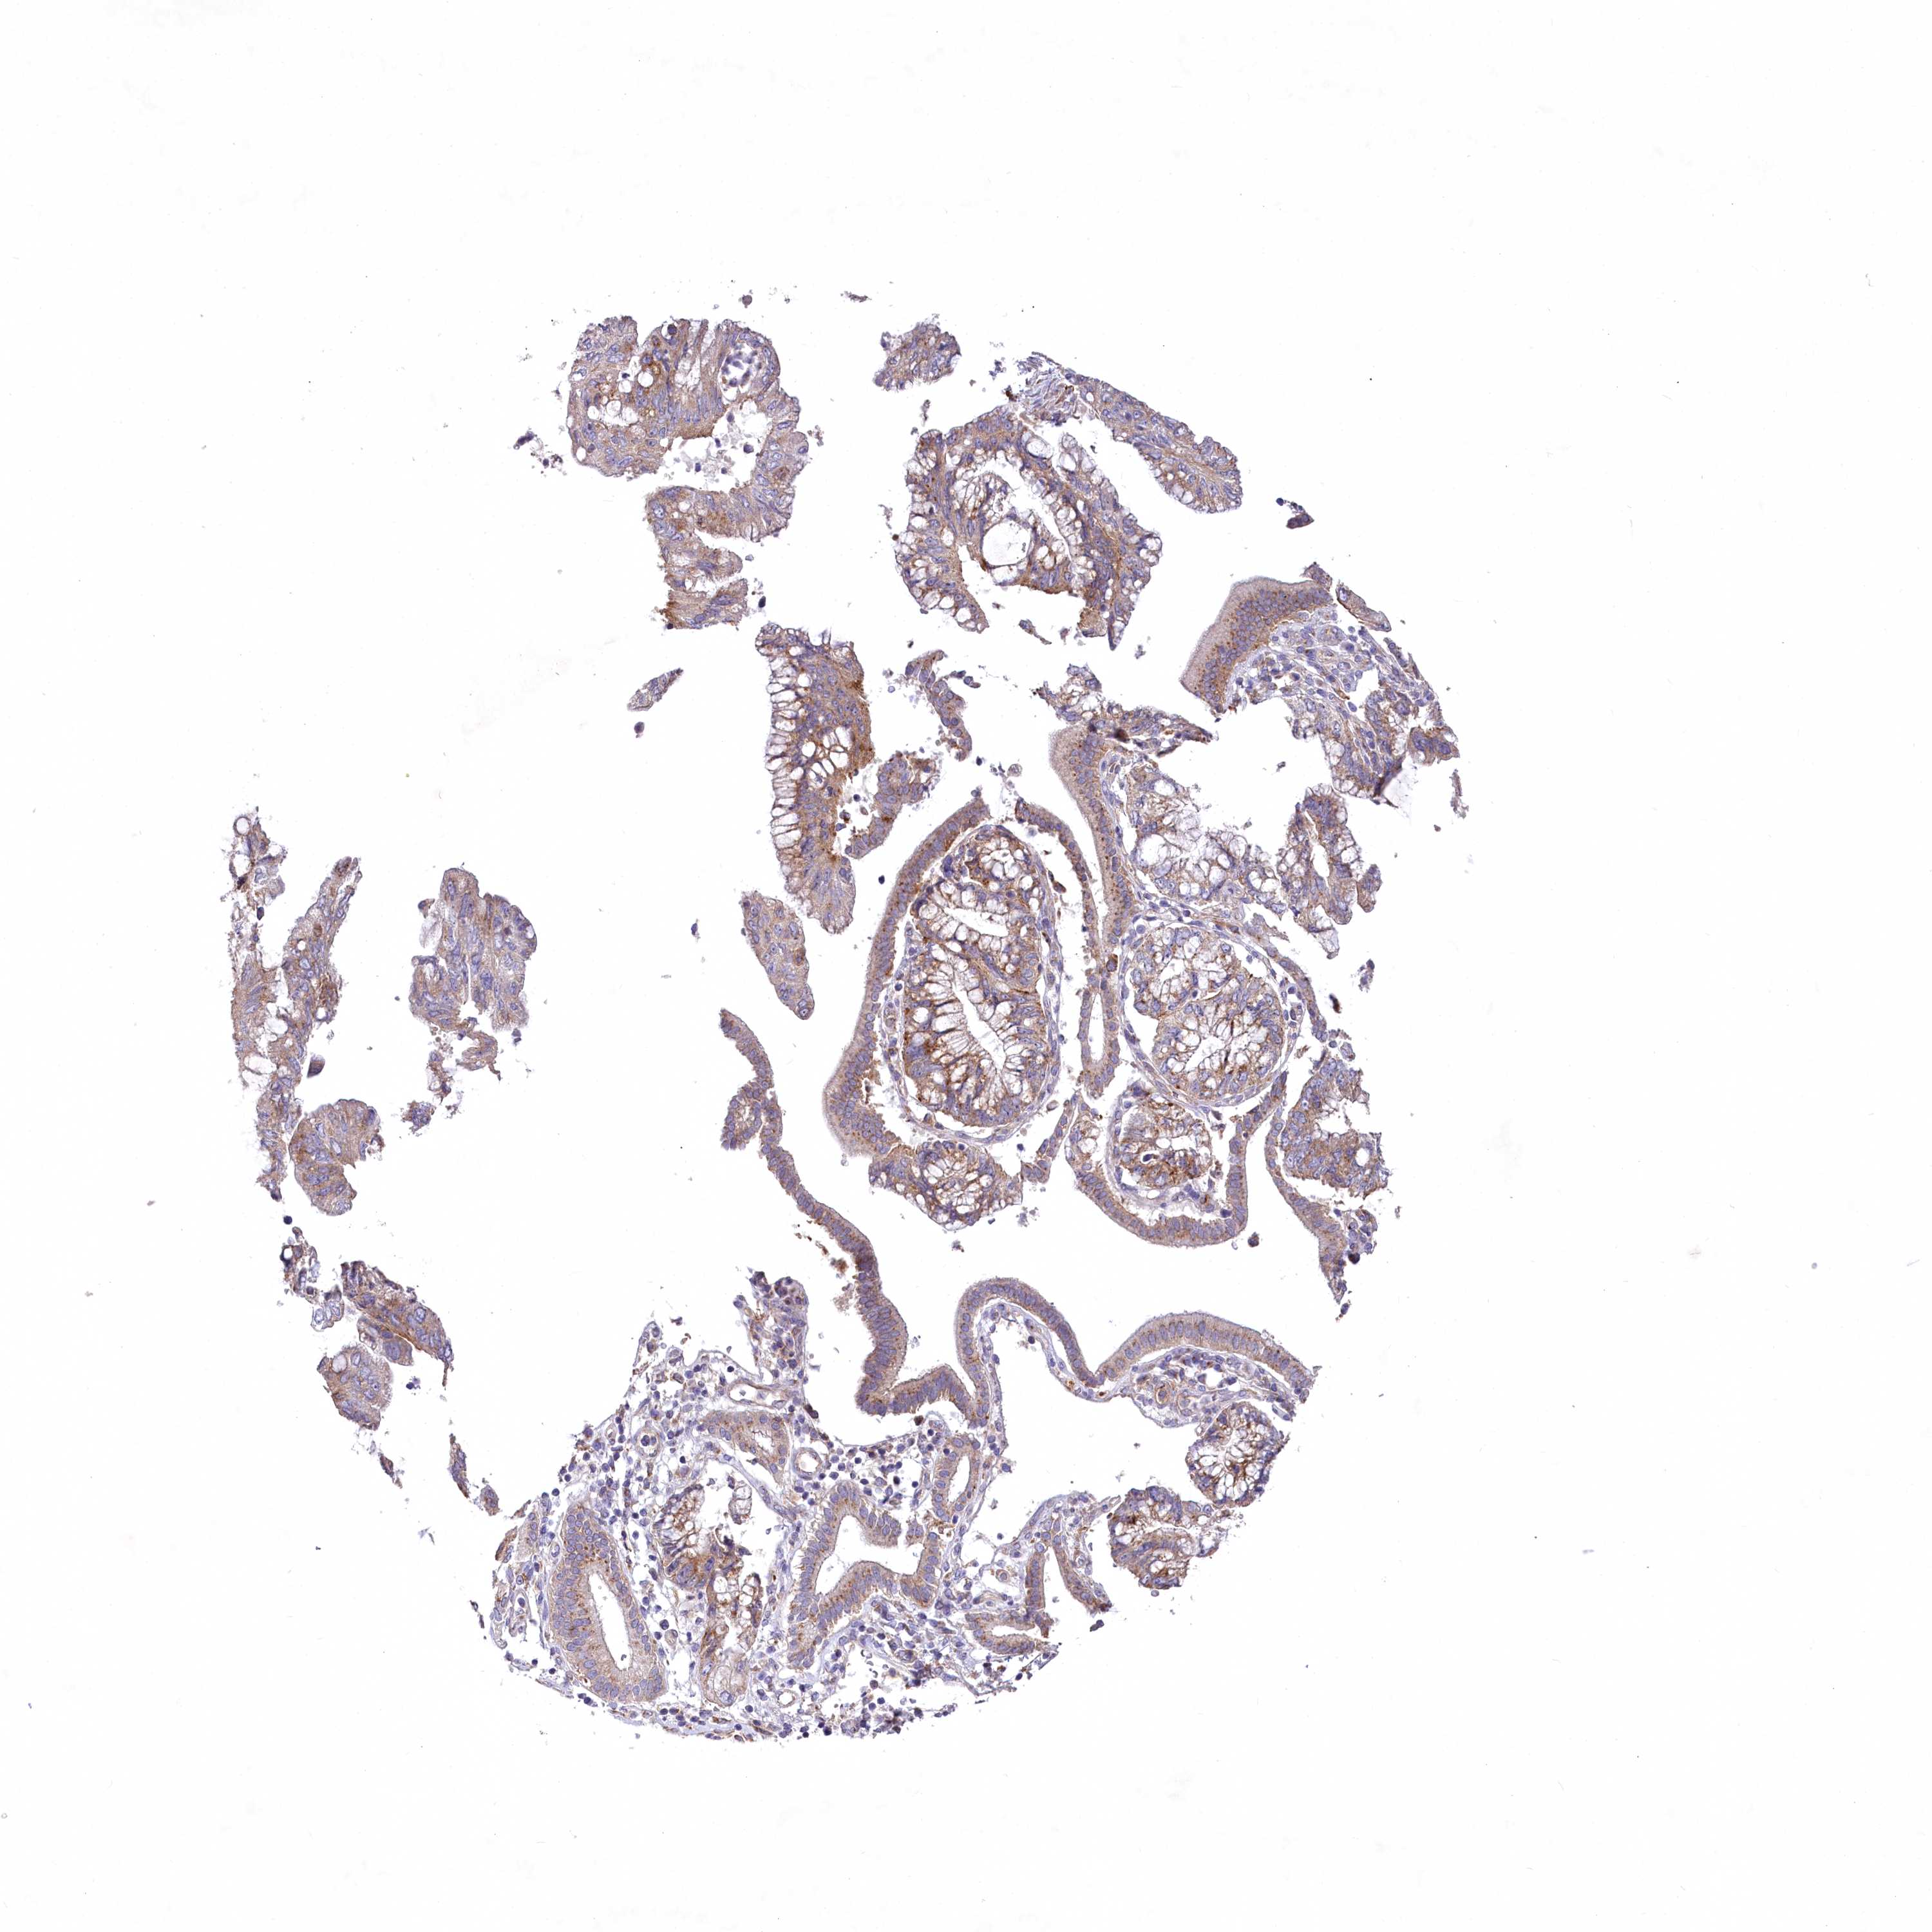

PANCREATIC CANCER - Protein expressioni

A mouse-over function shows sample information and annotation data. Click on an image to view it in a full screen mode. Samples can be filtered based on level of antibody staining by selecting one or several of the following categories: high, medium, low and not detected. The assay and annotation is described here.

Note that samples used for immunohistochemistry by the Human Protein Atlas do not correspond to samples in the TCGA dataset.

Antibody stainingi

Antibody staining in the annotated cell types in the current human tissue is reported as not detected, low, medium, or high, based on conventional immunohistochemistry profiling in selected tissues. This score is based on the combination of the staining intensity and fraction of stained cells.

Each image is clickable and will lead to virtual microscopy that enables deeper exploration of all samples and also displays staining intensity scores, fraction scores and subcellular localization as well as patient and tissue information for each sample.

Antibody HPA038557

Antibody HPA038558

Staining

High

Medium

Low

Not detected

Intensity

Strong

Moderate

Weak

Negative

Quantity

>75%

75%-25%

<25%

None

Location

Nuclear

Cytoplasmic/membranous

Cytoplasmic/membranous,nuclear

Adenocarcinoma, NOS